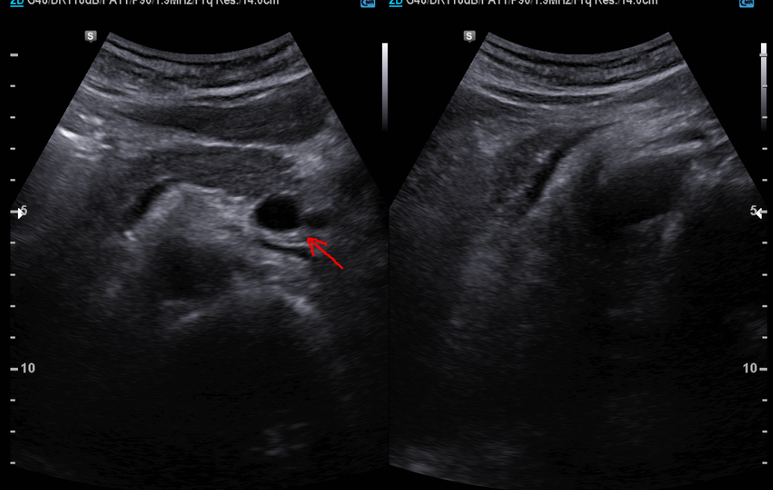

복부 초음파; 상장간맥 정맥이 좌측에서 관찰된다.